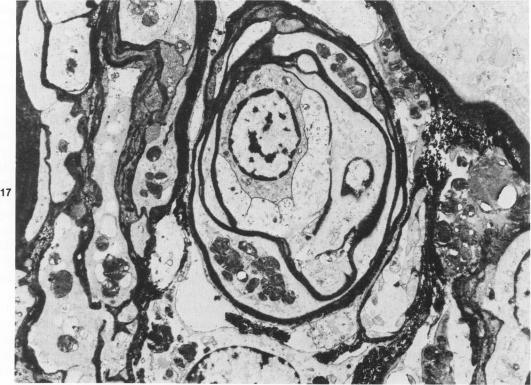

A histochemical study was performed on light- and electron-microscopic level in a case of Fabry's disease. The patient underwent kidney transplantation for renal failure and died of heart failure 6 months later. Patient's tissues were studied at the light- and electron-microscopic levels with various embedding and staining techniques for lipids and carbohydrates. Two peroxidase-labeled lectins (from Ricinus communis and from Bandeiraea simplicifolia) known to have affinity for alpha- and beta-D-galactose, were strongly reactive with the storage material on frozen sections. The ultrahistochemical and extraction tests showed that the typical granules had a variable reactivity and morphologic characteristics in different cells, probably reflecting different composition. A small number of typical deposits were also observed in the transplanted kidney. This is the first reported case of recurrence of the storage disease in the allograft. Of interest was also the fact that the patient's blood inhibited normal alpha-galactosidase activity, suggesting a possible inhibitor-related mechanism in the pathogenesis of the recurrence.

对一例法布里病患者进行了光镜和电镜水平的组织化学研究。该患者因肾衰竭接受了肾移植,6个月后死于心力衰竭。采用多种脂质和碳水化合物包埋及染色技术,在光镜和电镜水平对患者组织进行研究。两种已知对α-和β-D-半乳糖有亲和力的过氧化物酶标记凝集素(来自蓖麻和单叶豆),在冰冻切片上与储存物质有强烈反应。超组织化学和提取试验表明,典型颗粒在不同细胞中有可变的反应性和形态特征,可能反映了不同的组成。在移植肾中也观察到少量典型沉积物。这是首次报道的同种异体移植中储存疾病复发的病例。同样有趣的是,患者血液抑制了正常的α-半乳糖苷酶活性,提示复发发病机制中可能存在与抑制剂相关的机制。